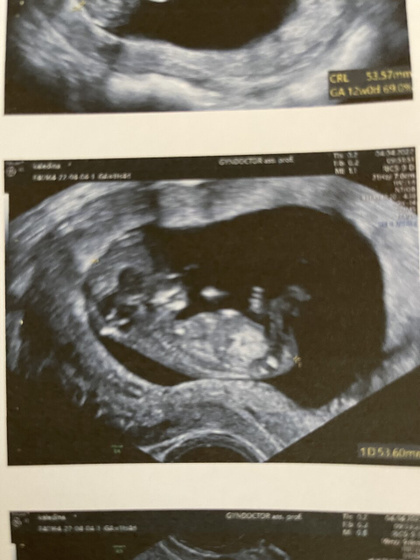

Были сегодня на первом скрининге. Я до этого всю ночь не спала, переживала очень, но все хорошо. Любимый держал меня за руку и наблюдал на экране за малышом, он то его в первый раз увидел! Впечатлился, весь день ходит, животик мой гладит ?

Малыш в норме, соответствует сроку, пол пока не видно. Отслойка хориона затянулась, осталась лишь маленькая гематома, врач сказала, что видно, что уже рассасывается.

Мне кажется у вас мальчик ?

Почему?? По фото?? Хотя и мне кажется, мальчик ? а так хотелось девочку ?

Там не видно кто, но вот такое ощущение когда на фото смотришь ? у вас первый ребёнок?